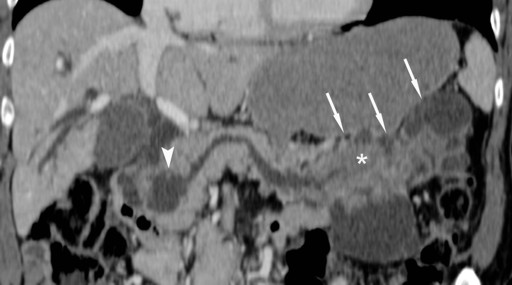

CT (Somatom Definition, Siemens Medical Solutions, Forchheim, Germany) confirmed the cystic lesion in the pancreatic head and revealed another cystic lesion in the pancreatic tail. Both lesions contained several septae and solid elements which showed uptake of iodine-containing contrast media (Figure 1). The main pancreatic duct was dilated in the pancreatic head, body, and tail. Furthermore, dilatation of the common bile duct as well as of the intrahepatic bile ducts was found.

Figure 1. Curved coronal CT image of the pancreas in the portal venous phase of contrast enhancement. Communication of the mainly cystic intraductal oncocytic papillary neoplasm to the main pancreatic duct in the pancreatic head (arrowhead) and tail is clearly depicted (arrows). Please note the considerable size of the solid tumor part in the tail of the pancreas (asterisk). |